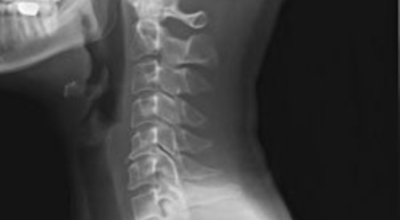

외부로부터 강력한 충격은 주로 교통사고로 인해서 발생돼요. 교통사고만 나면 주로 목을 잡게 되죠? 뒤차에 받혔을 때 주로 경추에 충격을 주어 주로 경추염좌 진단을 받는데 가벼운 증상일 때 빨리 치료를 해야 되므로 입원해서 치료를 받는게 좋아요. 퇴형성으로 목 디스크 증상이 조금씩은 다 있는데 이럴 때 교통사고 나면 병원 가서 X-Ray 촬영하면 디스크(경주 염좌) 진단을 받게 됩니다.

목디스크 증상이 나타날때 빨리 발견하여 비수술 치료를 받고 꾸준히 관리하는 것이 베스트이죠. 목디스크 환자 중 수술을 진행하는 환자는 2% 미만으로 현저히 적다고 해요. 수술을 진행하는 경우는 감각이 느껴지지 않는 마미증후군이나, 한쪽 다리가 눈에 띌 정도로 야윈 경우에만 진행하므로 올바른 자세 교정만으로도 충분히 호전될 수 있는 질병이죠. 목에 연관된 검사는 MRI나 CT를 이용해요. 그러나 전자의 경우 비용이 굉장히 비싸기 때문에 디스크 증세가 확실하다고 생각될 경우에만 선택적으로 하고 의무적으로 하는 건 아니니까 비용에 대해선 부담을 가지지 마시길 바래요.